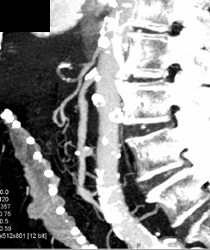

Nice IVC Opacification of Renal Veins